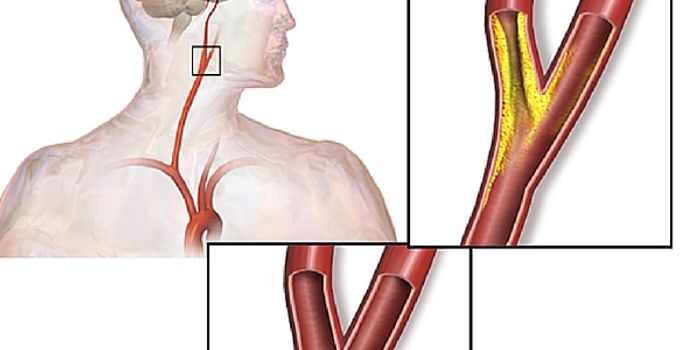

MAR 21, 2016NeuroscienceThe most common kind of stroke, an ischemic stroke, is caused by a blood clot which blocks the flow of oxygenated blood ...

MAR 17, 2016NeuroscienceBeauty parlor stroke syndrome? That can’t be a real thing right? Actually it is. There aren’t exact numbers ...

FEB 19, 2016CardiologyAt the recent International Stroke Conference of 2016, researchers presented a study that connected untreated high blood ...

JAN 28, 2016NeuroscienceWhen a patient suffers a stroke, the key factor is time. Neurologists call it a Golden Window where “time is brain ...

JAN 19, 2016NeuroscienceHaving a stroke can leave a person with significant impairments in movement, cognitive ability and speech. It is the thi ...

JAN 04, 2016NeuroscienceAs anyone who has survived a stroke can attest, recovery is often very difficult. Depending on the area of the brain, th ...

AUG 22, 2015NeurosciencePeople who work longer hours increase their risk of having a stroke, according to a new European study published recentl ...